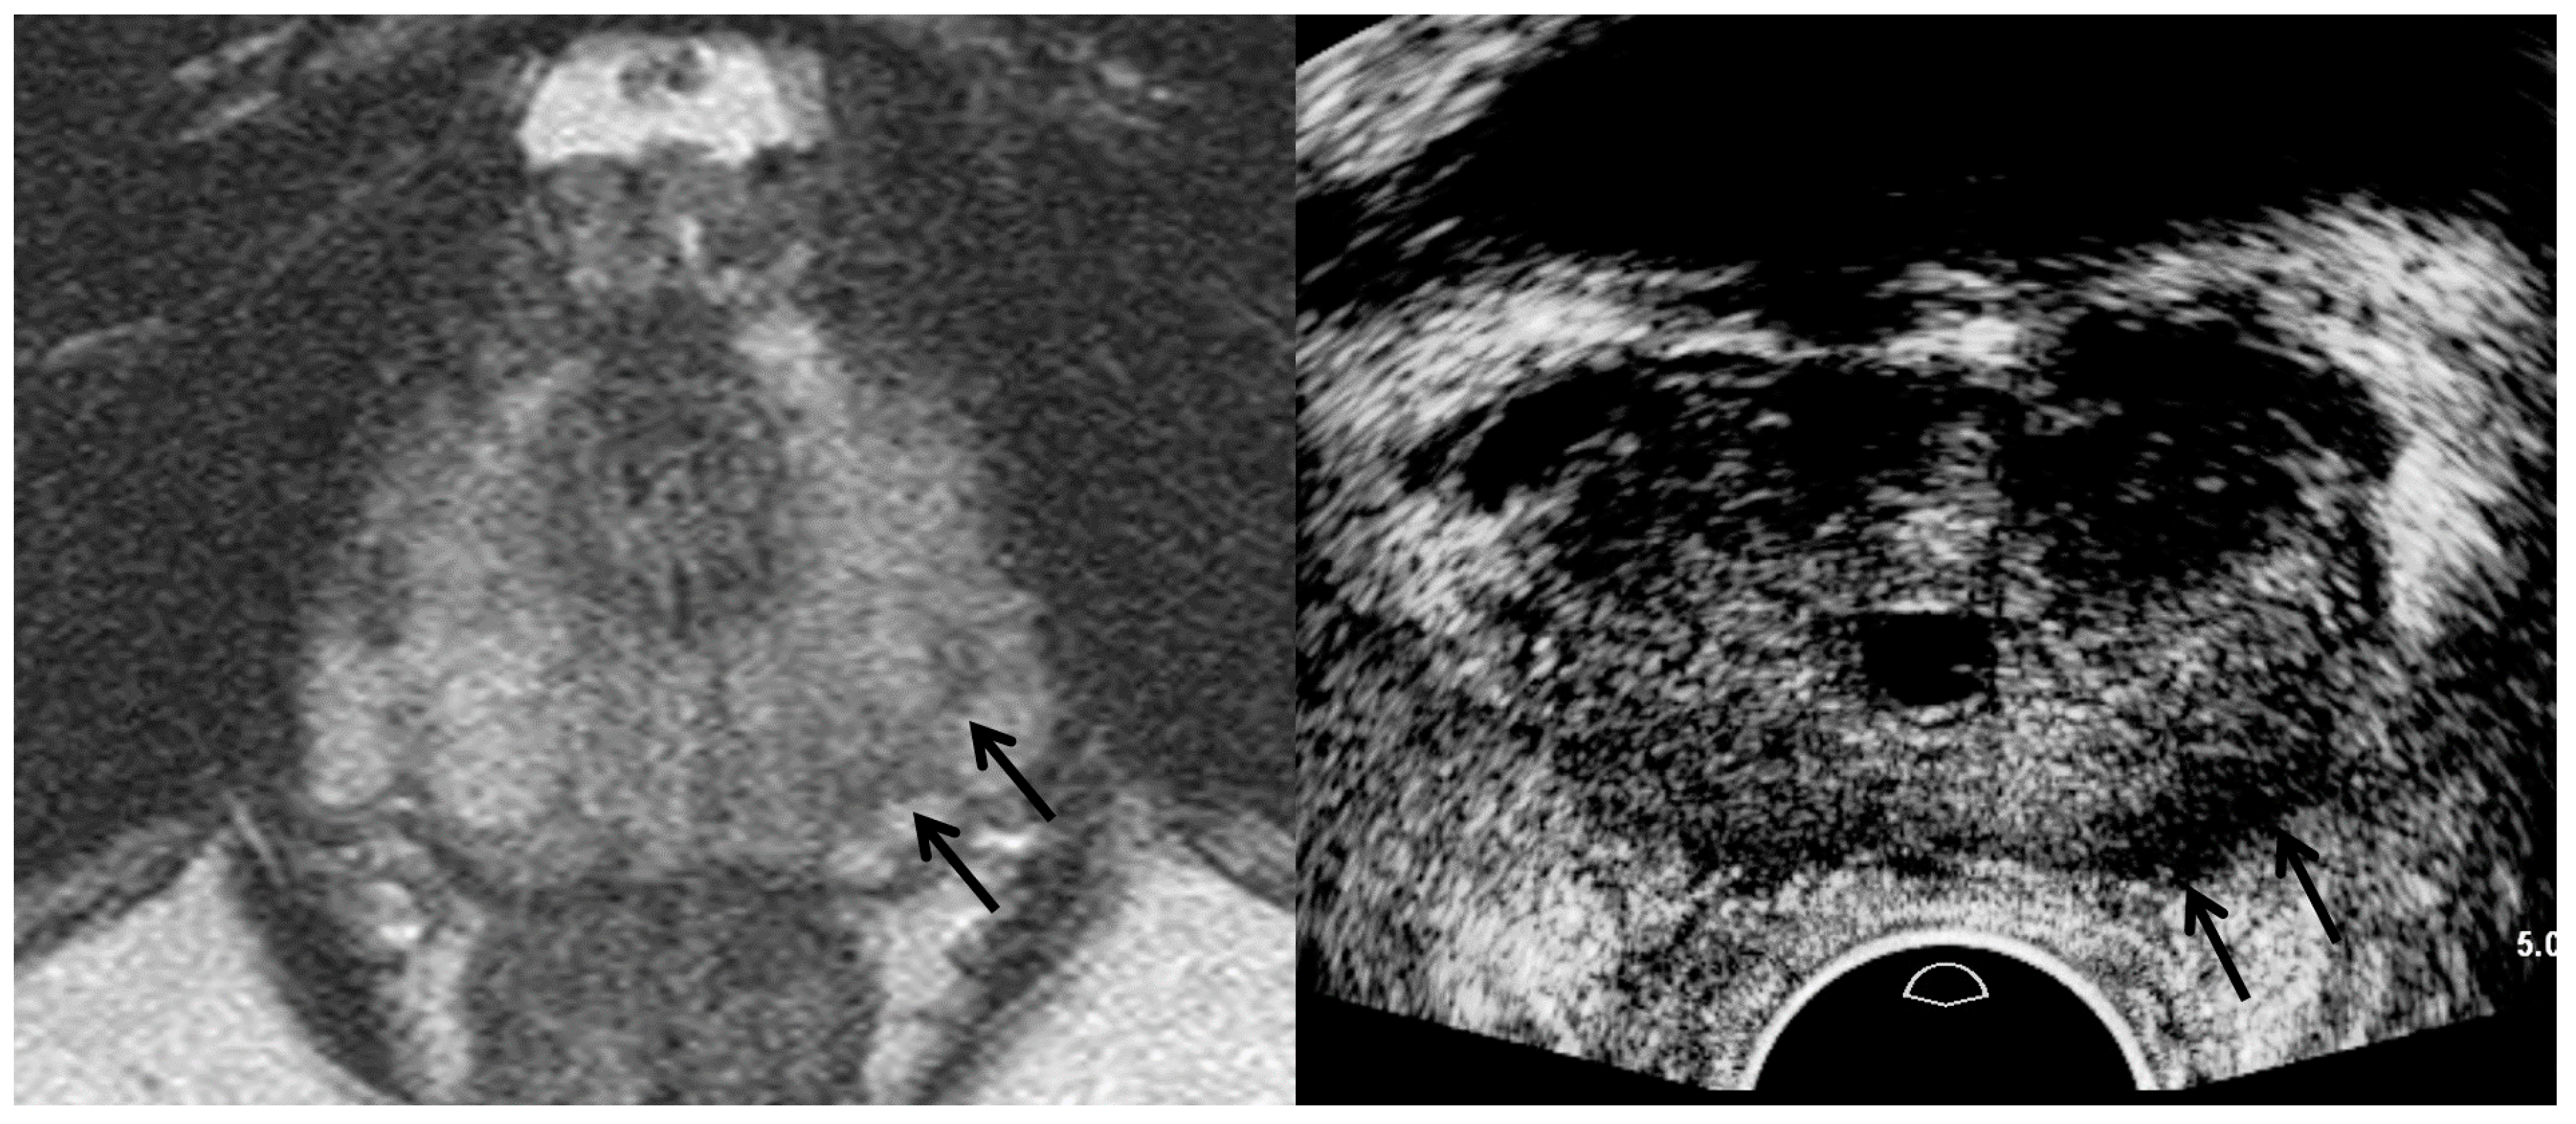

| TRUS Features | Peripheral Cancer | Transition Cancer | ||

|---|---|---|---|---|

| Insignificant Cancer | Significant Cancer | Insignificant Cancer | Significant Cancer | |

| Echogenicity | Low | Lower | High | Higher |

| Size | Small | Large | Small | Large |

| Echotexture | Homogeneous | Heterogeneous | Homogeneous | Heterogeneous |

| Margin | Smooth | Irregular | Smooth | Irregular |

| Perfusion | Low | High | NA | NA |

| Hypoechoic rim | NA | NA | Clear | Unclear |